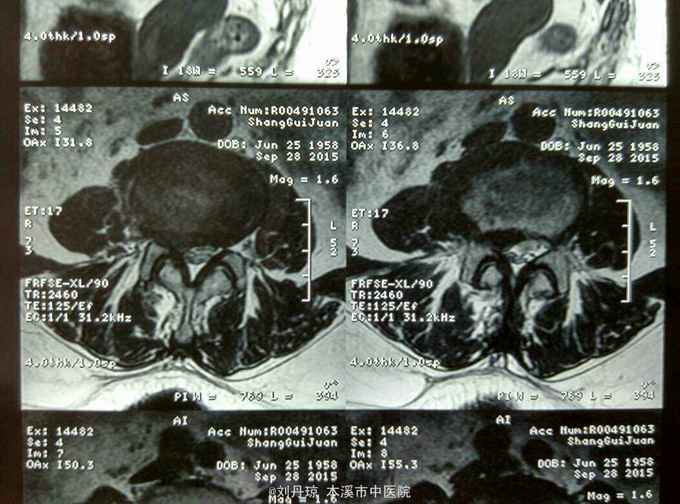

腰部疼痛伴右下肢放射痛麻木感半年,加重2月。患者半年前劳累后感到腰部疼痛伴右下肢放射痛麻木感,近2月病情加重来诊。

查体:L1—S1棘突右旁压痛阳性。直腿抬高实验左70度,右40度。 直腿抬高加强实验左侧阴性,右侧阳性。腰椎功能障碍。 辅查:CT: L1—S1椎间盘突出。

诊断:腰椎间盘突出症 治疗:针灸、雷火灸、中药熏药治疗、小针刀治疗、骶管注射治疗、营养神经药物治疗、脱水药物治疗,当归地黄饮加味。